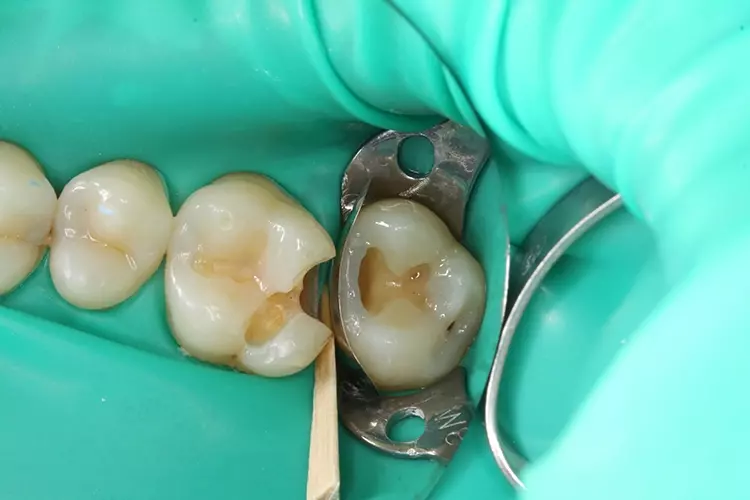

Um die Klasse-II- in eine Klasse-I-Kavität zu überführen, wurde zunächst die Randleiste mit einem hochviskösen Nanohybrid-Bulk-Fill-Komposit (GrandioSO x-tra, VOCO) aufgebaut (Abb. 5 und 6). Da das Material leicht modellierbar und die 0,04 mm dünne Stahlmatrize ausreichend stabil war, konnte bei diesem Schritt auf die Verwendung eines Matrizenrings verzichtet werden.

Dies erleichterte zudem die Übersicht und den Zugang für die Modellierinstrumente. Beim Aufbau der Randleiste war darauf zu achten, dass diese zum Nachbarzahn hin abgerundet wurde, um eine natürliche Einziehung zum späteren Einführen der Zahnseide sicherzustellen. Zur entsprechenden Formgebung diente ein spezieller Modellierspatel (Composite 4, American Eagle Instruments) (Abb. 5).

In der hier beschriebenen Falldokumentation wurde bei der relativ flachen Kavität an Zahn 27 zunächst nur die Randleiste aufgebaut und damit in eine Klasse-I-Kavität überführt (Abb. 5 und 6). Es folgte die Rekonstruktion der Okklusalfläche mit je einem Inkrement für den palatinalen und bukkalen Höckerabhang (Abb. 7). An Zahn 26 wurde wegen der schmalen, in mesiodistaler Richtung verlaufenden Kavität vorab keine primäre approximale Wand aufgebaut.